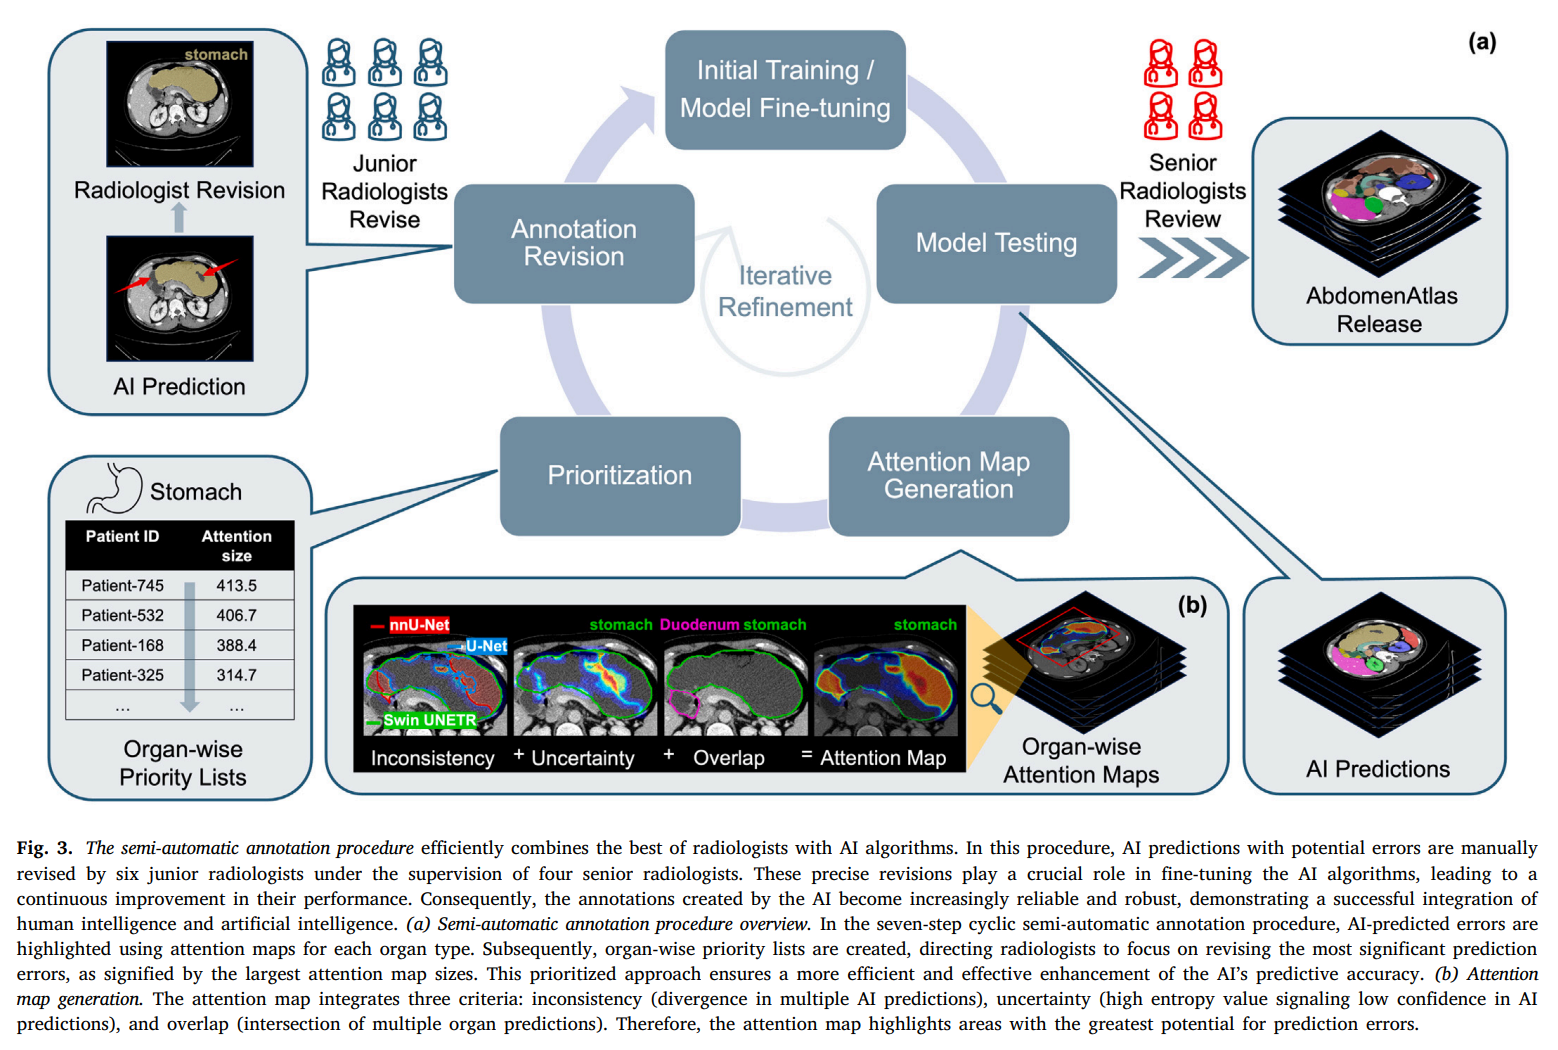

注释质量和一致性是我们构建AbdomenAtlas的首要任务。因此,我们首先建立了一个全面的注释协议和标准(第3.1节),旨在其他团队在构建类似数据集时可重复使用。基于该标准,我们应用了两种互补的注释程序。首先,我们采用了手动注释程序——放射科医生逐体素地注释每个CT体积,确保高质量但需要大量时间投入(第3.2节)。其次,我们采用了结合放射科医生专业知识和AI算法的半自动注释程序(第3.3节)——放射科医生根据突出潜在错误的注意力图修订AI预测。这种人机协同将创建大规模、详细注释数据集的效率提高了168倍。在发布之前,四名资深放射科医生需要验证AbdomenAtlas中的所有注释。

3.3 半自动注释程序

半自动注释程序结合了三种不同的AI算法——以最小化模型架构带来的偏差——在标记的CT体积的公共数据集上。这些AI算法为未标记的CT体积生成初始注释。我们开发了一种创新策略,可以找到AI预测中最重要的部分,并使用颜色协调的注意力图向放射科医生展示在手动审查AI工作时需要关注的区域(Qu等,2023;Li等,2024)。如图3所示,重复此过程——AI预测和人工审查——使我们能够将注释过程加速168倍。

3.3.1 注意力图揭示AI错误

我们开发了注意力图来突出AI预测中的潜在错误,指导放射科医生在审查和修订过程中。这些图为AI更可能犯错的区域分配更高的值,指示需要优先审查的区域。注意力图使用以下三个标准计算。

不一致性是来自三种AI架构(包括Swin UNETR、nnU-Net和U-Net)的软预测的标准差。具有高标准差的区域表示模型预测的高度分歧,提示需要额外的手动修订。不一致性 i , c _{i,c} i,c的计算公式为: